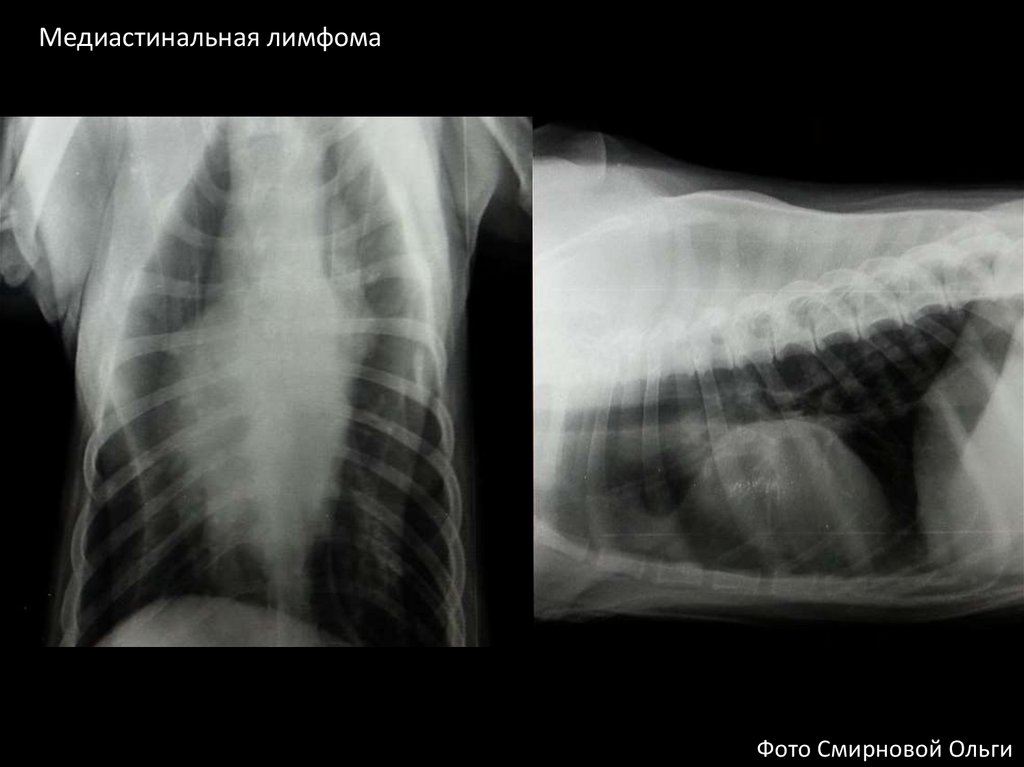

Медиастинальная лимфома

Фото Смирновой Ольги